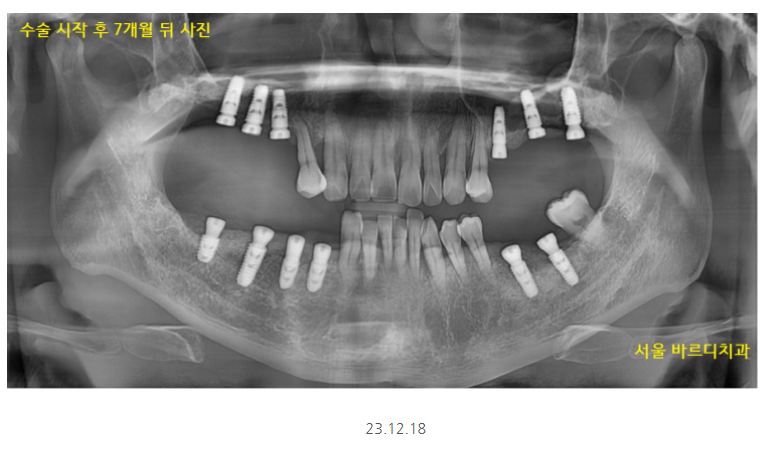

5월달에 왼쪽 위부터 수술했는데

7개월정도 지나 보철을 올려드렸어요

그동안 치아 상태는 이런 모습이셨어요.

길동 치과 완성 후 사진입니다.

정기점검때에도 흡연 계속 하시냐..

확인했던 기억이 있네요.

임플란트 오래 쓰실 수 있게 말이죠!

잇몸 청소 주기적으로 하는것 외에도

흡연이 구강에 미치는 영향

알려드리는 것이 저의 역할이니까요~